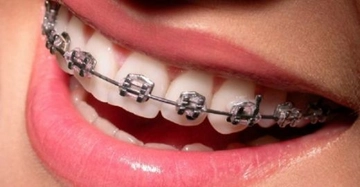

Beyaz diş telleri, dişlerin estetik görünümünü artırarak hizalanmasını sağlamak amacıyla kullanılan ortodontik bir tedavi yöntemidir. Seramik veya şeffaf malzemeden yapılan bu teller, hem konforlu bir kullanım sunar hem de estetik kaygıları azaltır. Ancak, maliyet ve bakım gereksinimleri gibi dezavantajları da bulunmaktadır. Bu yöntem, dişlerinde düzensizlik olan bireyler için uygun bir seçenek olabilir.

Beyaz Diş Teli Dişleri Düzeltir mi?Diş sağlığı ve estetiği, bireylerin genel görünümünü ve kendine olan güvenini doğrudan etkileyen önemli unsurlardır. Dişlerdeki düzensizlikler, sadece estetik kaygılar yaratmakla kalmayıp, aynı zamanda ağız sağlığına da olumsuz etkilerde bulunabilir. Bu nedenle, dişlerin düzeltilmesi amacıyla çeşitli ortodontik tedavi yöntemleri geliştirilmiştir. Beyaz diş telleri, bu yöntemlerden biri olarak son yıllarda popülarite kazanmıştır. Peki, beyaz diş telleri gerçekten dişleri düzeltir mi? Bu makalede, beyaz diş tellerinin işlevselliği, avantajları ve dezavantajları üzerinde durulacaktır. Beyaz Diş Teli Nedir?Beyaz diş telleri, ortodontik tedavi sürecinde dişlerin hizalanmasını sağlamak amacıyla kullanılan özel bir aparattır. Genellikle seramik veya şeffaf malzemeden üretilmektedir. Bu tür teller, klasik metal diş tellerine göre daha estetik bir görünüm sunar ve bu nedenle özellikle gençler ve yetişkinler arasında tercih edilmektedir. Beyaz Diş Tellerinin Avantajları

Sonuç Beyaz diş telleri, estetik açıdan daha hoş bir görünüm sunarak, dişlerin düzeltilmesi için etkili bir yöntemdir. Ancak, her bireyin diş yapısı ve ihtiyaçları farklı olduğundan, en uygun tedavi seçeneğini belirlemek için mutlaka bir uzmanla görüşülmesi gerektiği unutulmamalıdır. Beyaz diş tellerinin avantajları ve dezavantajları dikkatlice değerlendirildiğinde, bu tedavi yöntemi pek çok kişi için ideal bir çözüm olabilir. Ekstra Bilgiler: Diş sağlığı, genel sağlık ile doğrudan ilişkilidir. Dişlerdeki düzensizlikler, çiğneme sorunlarına ve diş eti hastalıklarına yol açabilir. Bu nedenle, ortodontik tedavi sürecini ihmal etmemek ve gereken önlemleri almak oldukça önemlidir. Diş sağlığınıza dikkat etmek, sadece estetik bir kaygı değil, aynı zamanda genel sağlığınızı korumak adına da büyük bir adımdır. |